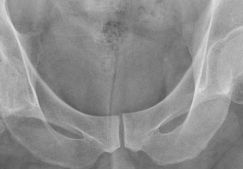

Эндопротезирование голеностопного сустава: показания, операция и реабилитация

Эндопротезирование голеностопного сустава: показания к операции, период реабилитации. Отличия от артродеза. Разновидности имплантов.